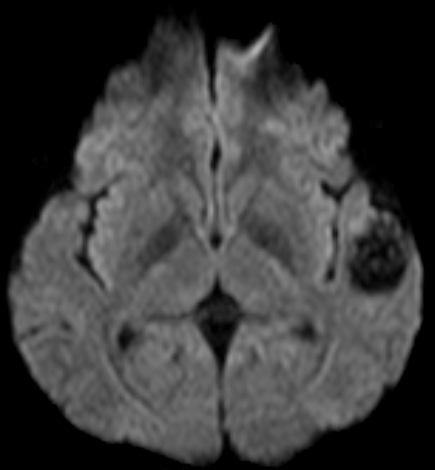

Khoa Chẩn đoán hình ảnh đã tiến hành chụp MRI sọ não với các xung MRA, MRV, dựng hình mạch máu não. Kết quả cho thấy, Bệnh nhân bị dị dạng mạch máu não (AVM) vùng thái dương bên trái có nguồn cung cấp máu từ động mạch não giữa cùng bên (bên trái), tĩnh mạch hồi lưu về xoang tĩnh mạch bên (bên trái).

Hình ảnh tổn thương

DWI